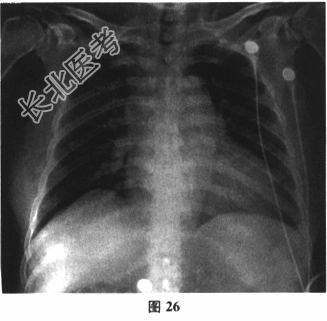

入院心电图如图25所示, 胸部X线片如图26所示。超声心动图:左房、左室扩大, 左室下壁及室间隔心尖段收缩运动减弱。心包探及液性暗区3mm,二尖瓣关闭不全(中度), 三尖瓣关闭不全(轻度),主动脉瓣钙化明显, 左室EF45%。